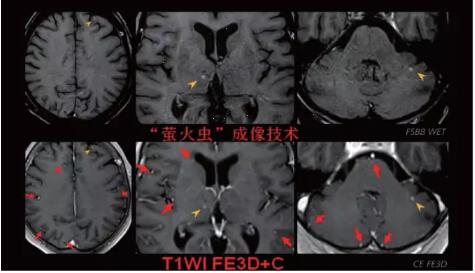

見所未見 微小腫瘤無處遁藏——

“螢火蟲”成像技術(shù) 顱內(nèi)腫瘤微小病灶檢出新發(fā)現(xiàn)

此技術(shù)主要用于神經(jīng)系統(tǒng)惡性腫瘤,以及其他腫瘤腦轉(zhuǎn)移瘤篩查。傳統(tǒng)情況下做腫瘤腦轉(zhuǎn)移篩查,很容易漏掉5mm以下小病灶,臨床發(fā)現(xiàn)后干預(yù)治療比較晚,要實(shí)現(xiàn)2mm高空間分辨率和超薄層全腦掃描在保證信噪比的情況下需要很長時(shí)間大概十多分鐘,而且薄層增強(qiáng)序列顱內(nèi)血管呈高亮信號,會(huì)干擾顱內(nèi)小病灶的觀察,血管和小病灶區(qū)分困難。佳能”螢火蟲”成像技術(shù)既可以實(shí)現(xiàn)高空間分辨率和超薄層(最薄可實(shí)現(xiàn)0.2mm)全腦掃描,掃描時(shí)間短,2-3分鐘即可實(shí)現(xiàn)全腦3D掃描,同時(shí)避免了血管高亮信號的干擾,對顱內(nèi)原發(fā)或繼發(fā)的微小腫瘤檢查有重大意義。“螢火蟲”成像技術(shù)具有磁敏感效應(yīng),對于亞急性血敏感敏感,可以區(qū)分出血和強(qiáng)化的腫瘤。